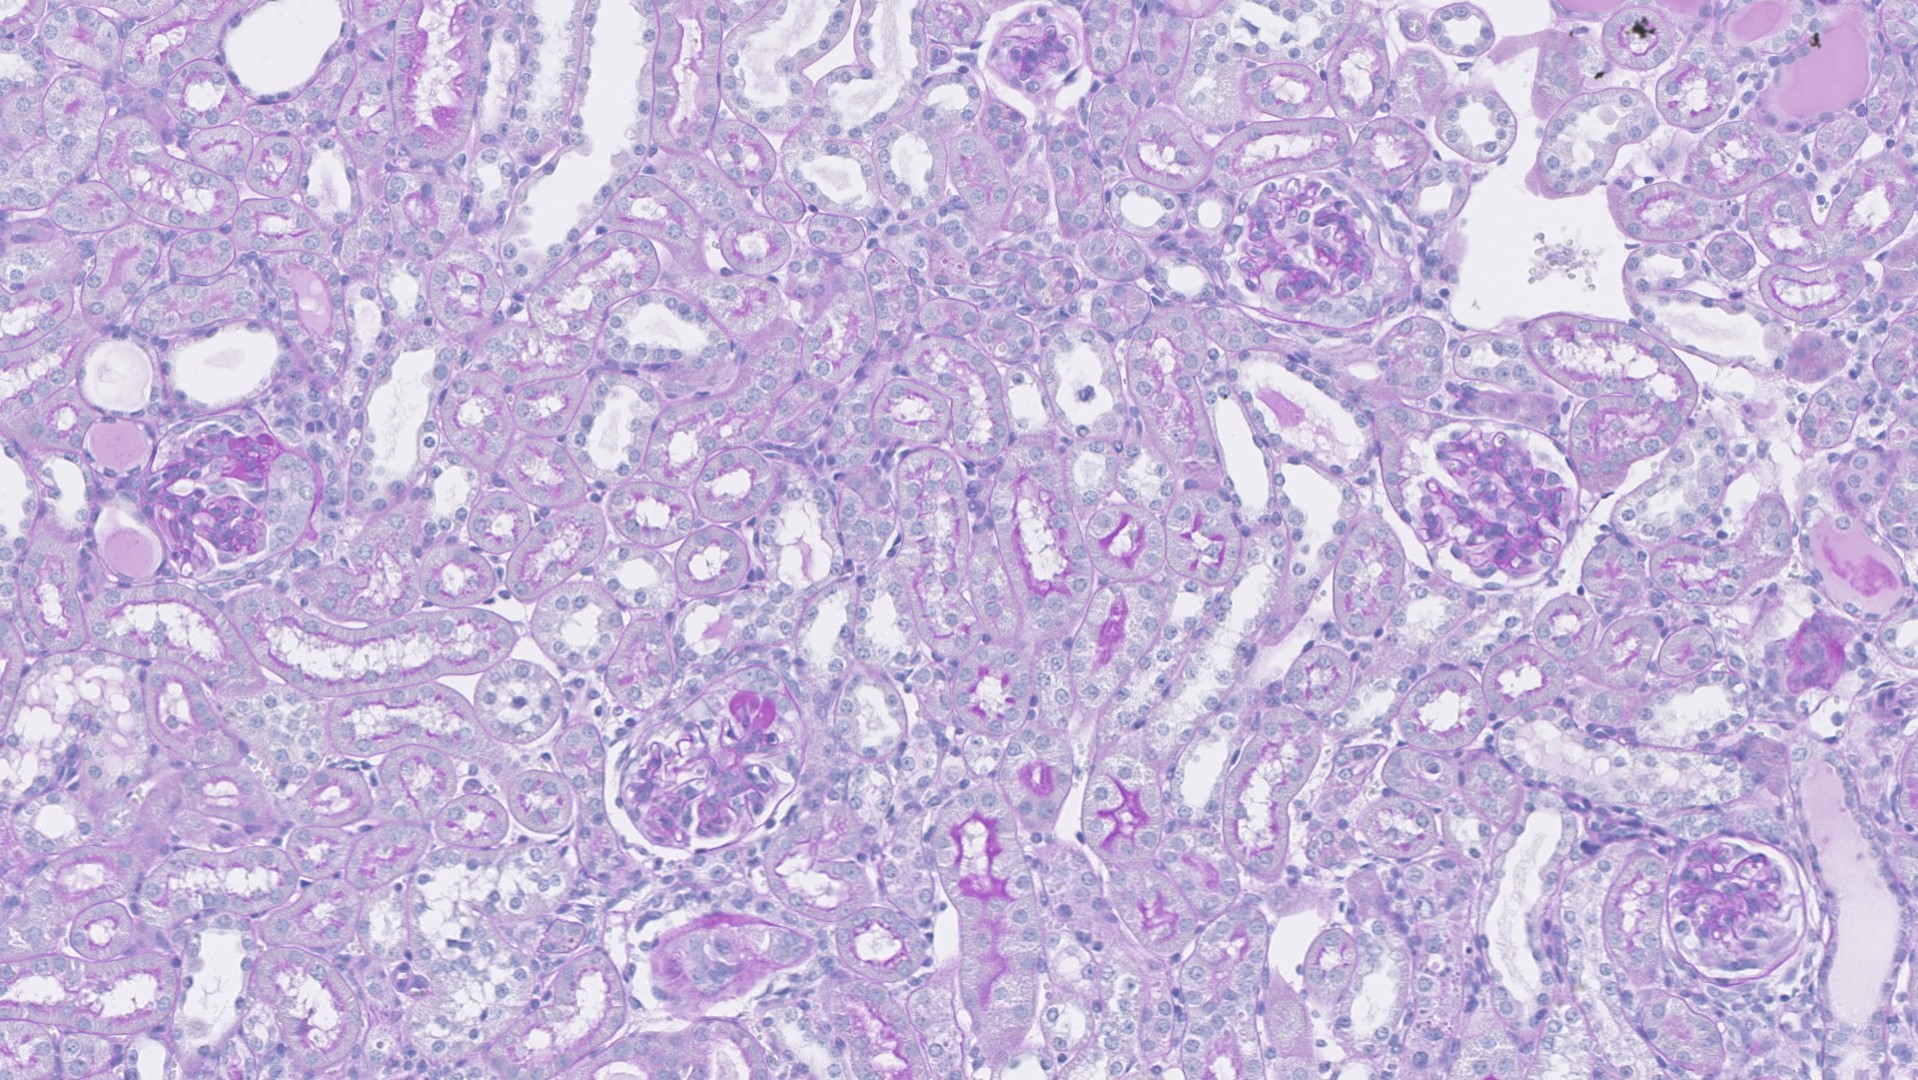

Lame scannée de rein de souris dans un modèle de hyalinose segmentaire et focale induite par l’intoxications aux glucocorticoides.

© Université Paris Cité/Inserm